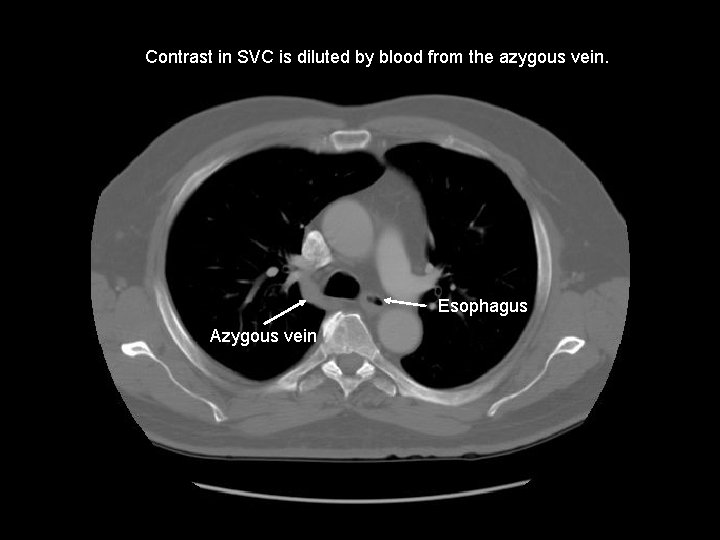

Contrast in SVC is diluted by blood from the azygous vein. Esophagus Azygous vein